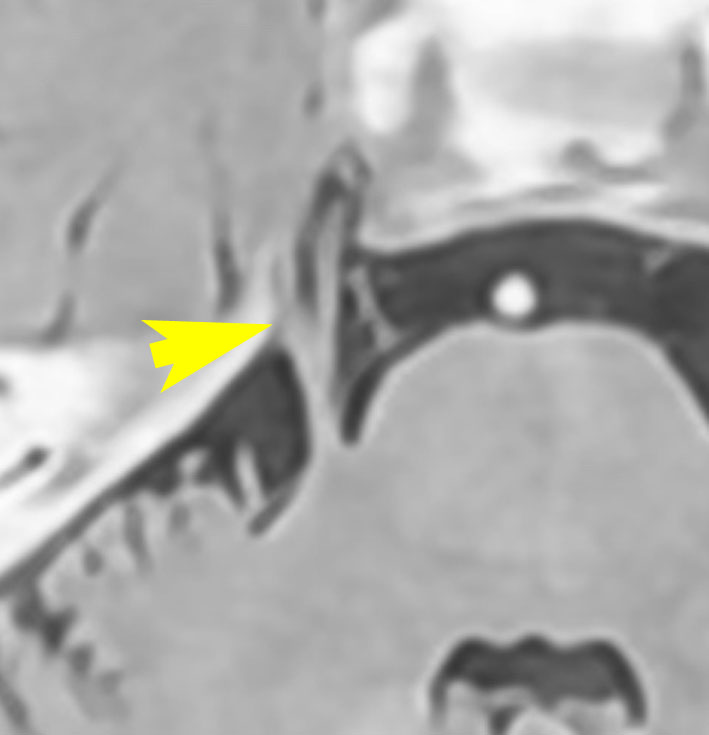

左側の写真は,顔面神経の根っこを前下小脳動脈が圧迫しているところです。矢印が示すのは,脳から顔面神経が出たところ(REZ レズ)です。ここが圧迫されないと顔面けいれんは起こりません。右側の写真は,動脈をよけて顔面神経のREZを解放したところです。長い間の圧迫でちょっとヘコんでいます。これが最も多いタイプです。